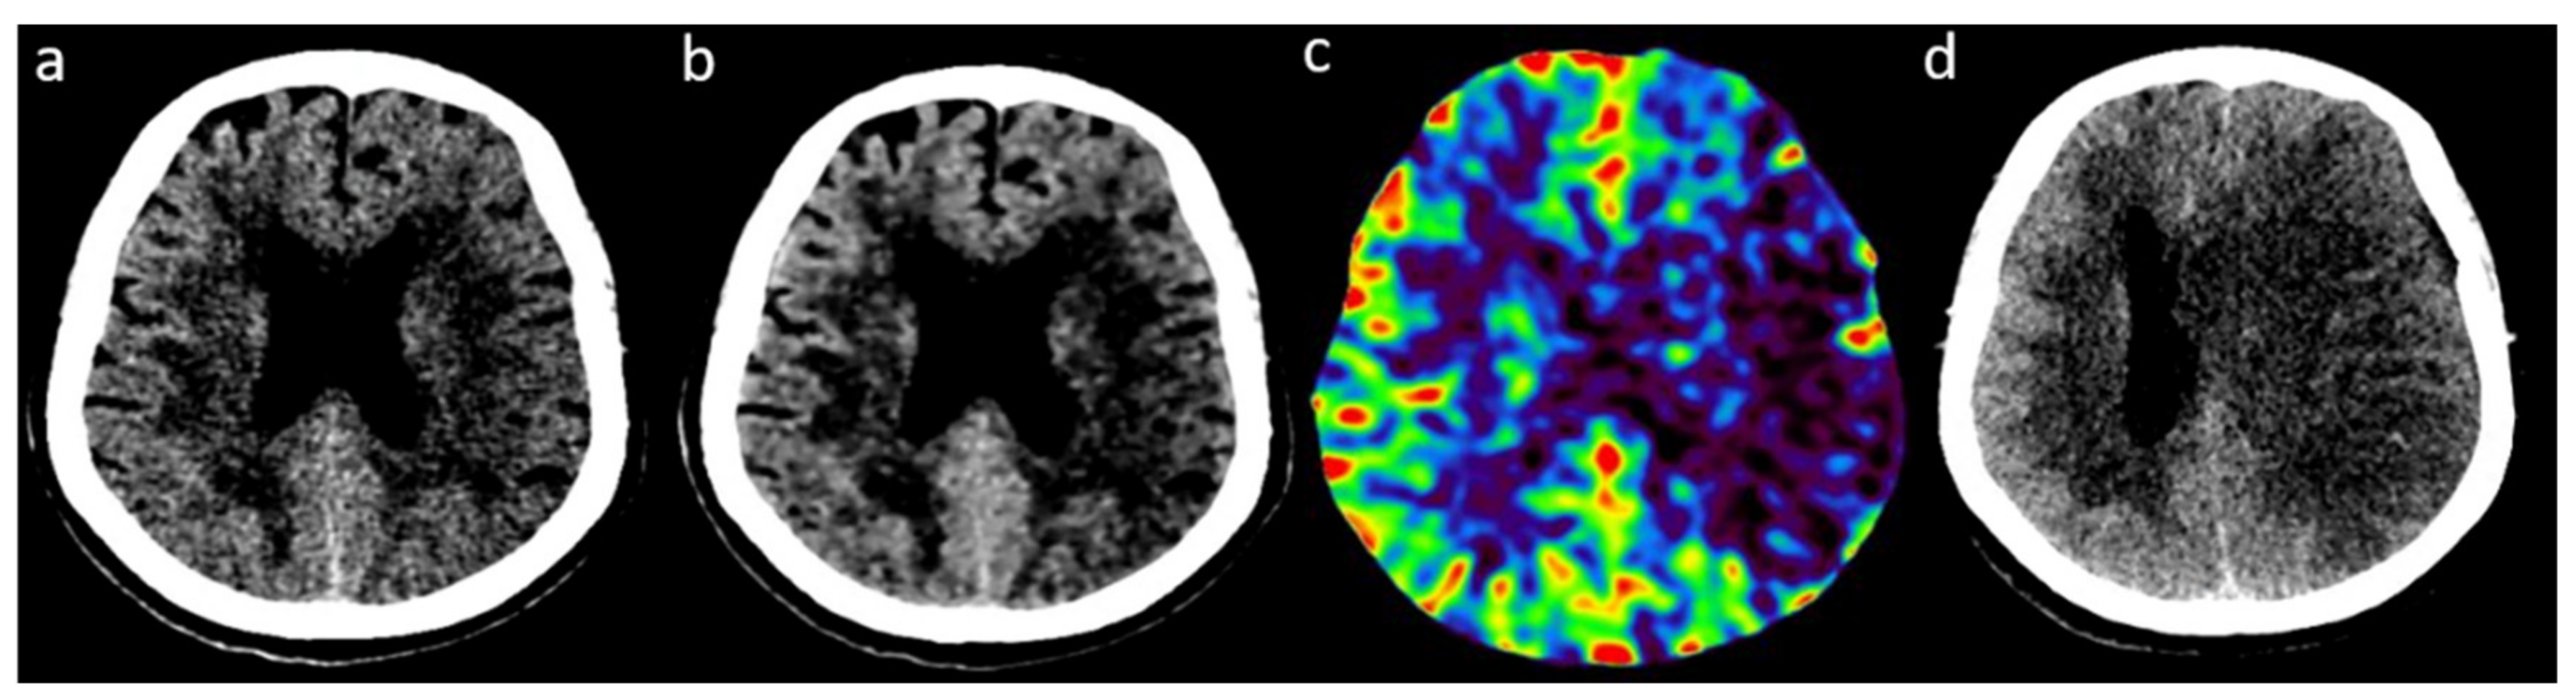

2.2. Image Acquisition and Reconstruction

2.3. Readings of FIRST-LCD and AIDR3D ASPECTS on Baseline NCCT